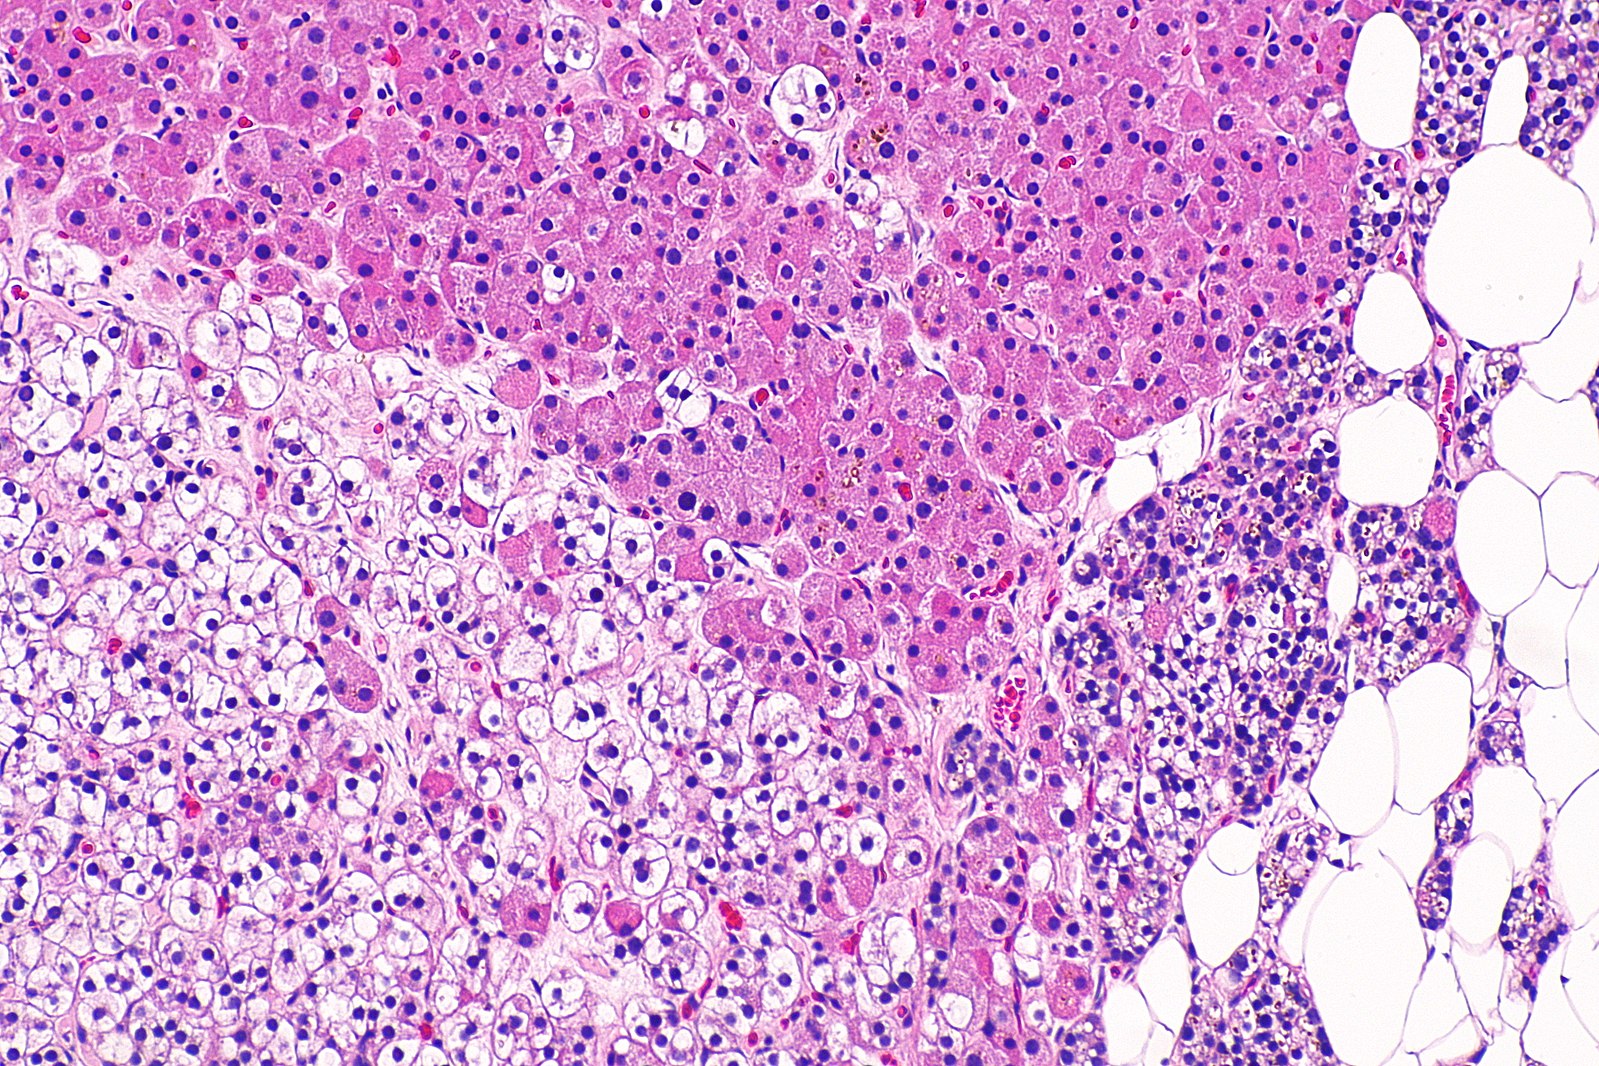

[8]Image credit: https://commons.wikimedia.org/wiki/File:Parathyroid_adenoma,_mixed_type_--_intermed_mag.jpg